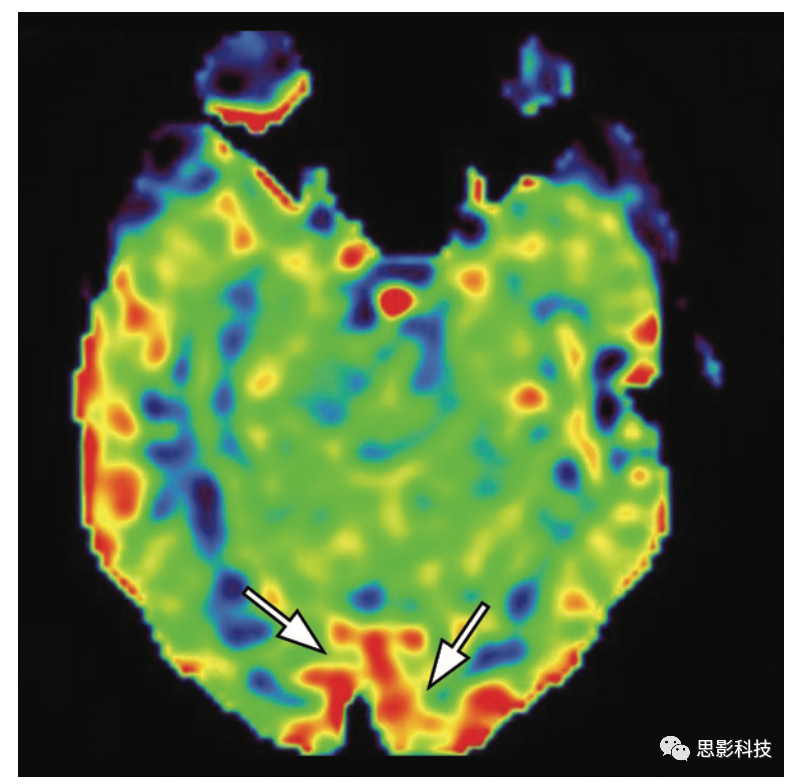

小腦神經(jīng)機(jī)能聯(lián)系不能 小腦神經(jīng)機(jī)能聯(lián)系不能是一種功能、代謝和血流灌注的抑制,由于對(duì)側(cè)幕上病變而影響小腦半球(11)ASL可能顯示幕上病變的對(duì)側(cè)小腦半球CBF降低。

11 一位68歲男性患者,患有交叉性小腦神經(jīng)機(jī)能聯(lián)系不能,有右側(cè)大腦中動(dòng)脈區(qū)域的中風(fēng)病史。

(AB)軸位FLAIR MRI顯示缺血性腦梗塞的后遺癥,右側(cè)皮質(zhì)脊髓束有華氏變性(B中的箭頭),并在彌散張量纖維束成像(未顯示)中得到證實(shí)。

(C)ASL MRI顯示左側(cè)小腦半球低灌注,其特征為交叉性小腦神經(jīng)機(jī)能聯(lián)系不能(箭頭)。